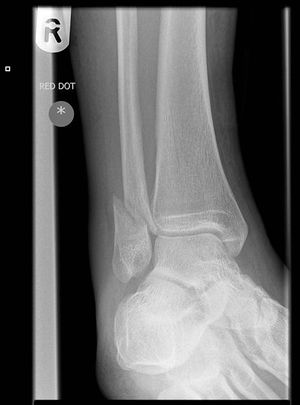

- AP: Best for isolated lateral and medial malleolar fractures

- Oblique (mortise)

- Best for evaluating for unstable fracture or soft tissue injury

- At a point 1 cm proximal to tibial plafond space between tib/fib should be ≤6mm

- Lateral: Best for posterior malleolar fractures

Classification (Danis-Weber System)

- system based on level of the fibular fracture and characterizes stability of fracture

- tibial plafond and the two malleoli is referred to as the ankle "mortise" (or talar mortise)

Type A

- fibula fracture below ankle joint/distal to plafond

- medial malleolus often fractured

- tibiofibular syndesmosis intact

- usually stable: occasionally requires ORIF

Type B

- fibula fracture at the level of the ankle joint/at the plafond

- can extend superiorly and laterally up fibula

- tibiofibular syndesmosis intact or only partially torn

- no widening of the distal tibiofibular articulation

- medial malleolus may be fracture

- possible instability

Type C

- fibula fracture above the level of the ankle joint/proximal to plafond

- tibiofibular syndesmosis disrupted with widening of the distal tibiofibular articulation

- medial malleolus fracture

- unstable: requires ORIF